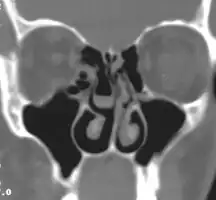

Right concha bullosa with air fluid level within